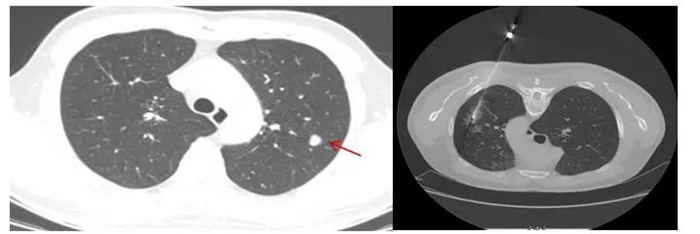

CT引導(dǎo)下肺穿刺活檢,8毫米肺結(jié)節(jié)排除肺癌可能

黃先生肺結(jié)節(jié)的性質(zhì)變得難以確定,經(jīng)評(píng)估,金旭如帶領(lǐng)呼吸介入團(tuán)隊(duì)給黃先生行肺穿刺活檢。

“通過(guò)CT掃描測(cè)量,確定穿刺進(jìn)針點(diǎn)、方向、距離,使用肺穿刺針經(jīng)胸壁穿刺到肺結(jié)節(jié)部位,進(jìn)行3~4次切割取材,獲取組織送檢驗(yàn)及病理切片?!睉c幸的是,穿刺結(jié)果顯示,黃先生的肺結(jié)節(jié)為:肺隱球菌病。

CT定位下經(jīng)皮肺穿刺活檢

行CT引導(dǎo)下經(jīng)皮肺穿刺活檢術(shù)前,患者需要排除近期服用抗凝藥物、自身凝血障礙等禁忌癥,術(shù)前完善CT增強(qiáng)掃描,以顯示肺結(jié)節(jié)與周?chē)芊植嫉年P(guān)系,明確穿刺時(shí)的位置選取,最大程度避免傷及血管,減少出血風(fēng)險(xiǎn)。